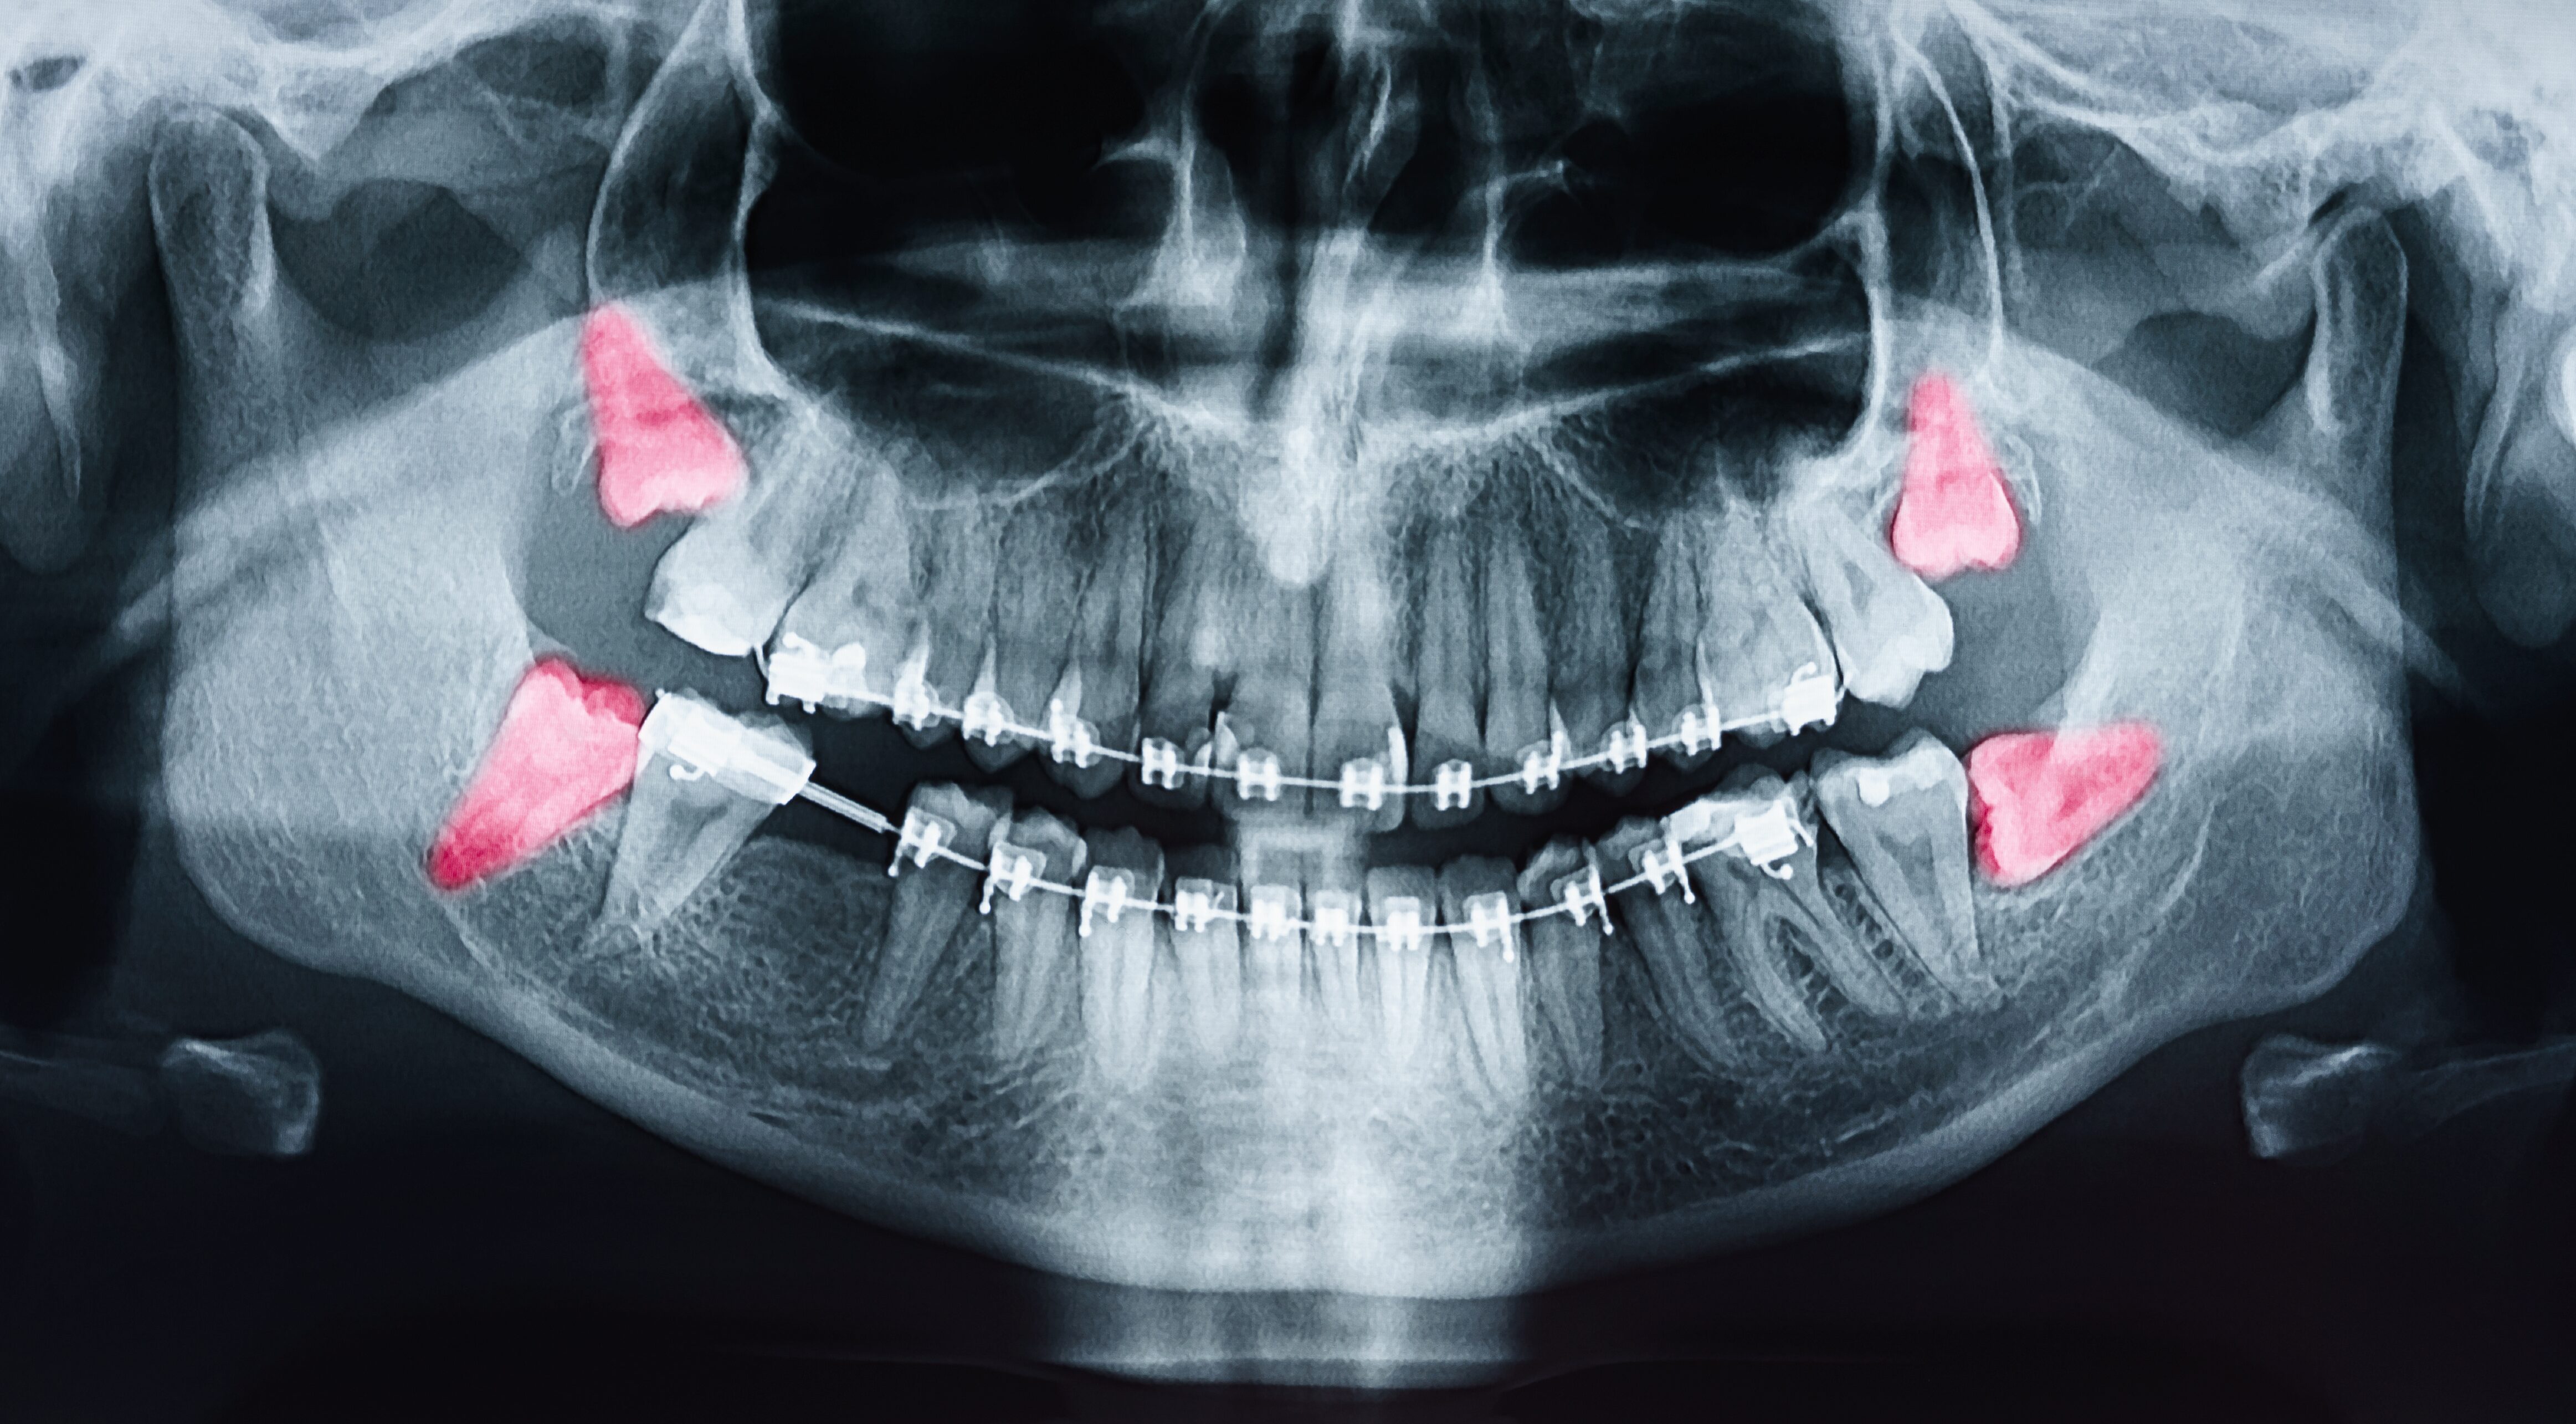

In der modernen Zahnmedizin ist das Röntgen ein elementarer Bestandteil, wenn es darum geht, die Zahngesundheit des Patienten festzustellen. Mit dieser Technik ist es möglich, den Bereich zwischen den Zähnen einzusehen, sowie den Zustand im Inneren eines Zahnes und seine Wurzeln im Kieferknochen zu untersuchen.

Dieses bewährte Verfahren haben wir in unserer Praxis auf den neuesten Stand der Technik gebracht: Bei uns findet nun das digitale Röntgen Anwendung. Die Vorteile für uns als Mediziner, aber auch für Sie als Patienten sind dabei deutlich spürbar: Die Qualität und Handhabung der Aufnahmen ist besser und einfacher. Die Bilder stehen unmittelbar nach der Aufnahme am Computer zur Verfügung. So lassen sich Bereiche gezielt vergrößern und bewerten, der Kontrast ist zu justieren, was eine bessere Bildqualität mit sich bringt und wir so den Beschwerden noch genauer auf den Zahn fühlen können. Vor allem aber wird die Strahlenbelastung, der sie beim Röntgen ausgesetzt sind, mit diesem modernen Verfahren um rund 90% reduziert.